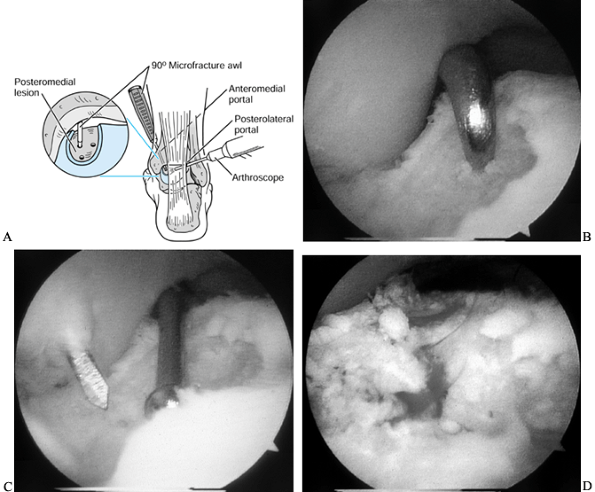

Insert a 90° microfracture awl for small lesions (Fig. 93.14A).![]() Figure 93.14. (See COLOR FIG. 93.14B, COLOR FIG. 93.14C and COLOR FIG. 93.14D). Arthroscopic treatment of osteochondral lesions of the talus. A: Figure 93.14. (See COLOR FIG. 93.14B, COLOR FIG. 93.14C and COLOR FIG. 93.14D). Arthroscopic treatment of osteochondral lesions of the talus. A:

The left ankle is shown. Viewing from the posterolateral portal, a

subchondral bone of a posteromedial lesion. B: Microfracture of the subchondral surface using an awl. C: Using a drill guide for transmalleolar drilling of the subchondral bone. D: The result of the above two treatments is a bleeding bone surface providing vascular access for cartilage formation.

For larger lesions, use a 90°

microfracture awl along the peripheral edge of the lesion and use a

MicroVector (Smith and Nephew, Endoscopy, Andover, MA) to drill

multiple holes in the center of the lesion (Fig. 93.14B and Fig. 93.14C; see COLOR FIG. 93.14B, COLOR FIG. 93.14C and COLOR FIG. 93.14D).